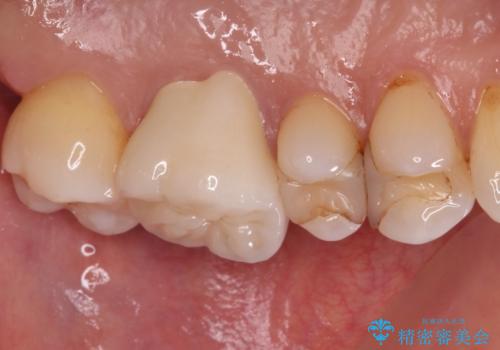

セラミッククラウンを装着する前に仮歯を装着しましたが、その時点で痛みはほぼ改善され、セラミッククラウン装着後には痛みが感じることはもちろん、見た目にも気になる点はなくなりました。